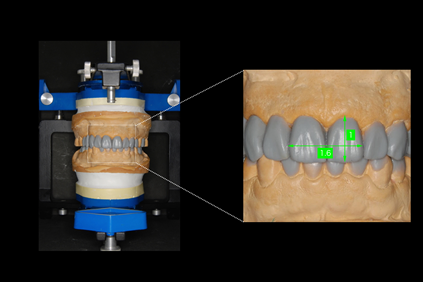

審美歯科では、1本1本の歯の形・プロポーションが重要です。

最も美しいとされる「黄金率(1:1.618)」をベースに、美しい歯の形へ整えていきます。